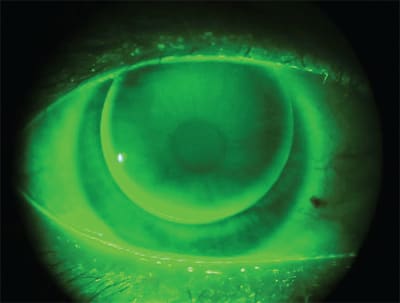

One essential aspect of fitting GP lenses is carefully assessing the lens-to-cornea fitting relationship with fluorescein, including both the central and peripheral fluorescein pattern. Use a Wratten filter to allow for best viewing. The optimal pattern shows very mild clearance throughout to the periphery with slightly greater clearance peripherally. Click N' Fit, one of the many resources available at www.gpli.info, provides an excellent overview of fluorescein patterns (Figure 1) and what occurs when you make changes to base curve radii and diameter.

Figure 1. On-K base curve radius from Click N' Fit.

If there is excessive edge clearance, which results from a very flat and wide peripheral curve or from apical bearing, the patient could experience increased lens awareness due to lift off at the lens edge. The completeness of the blink may be compromised, resulting in increased potential for 3 o'clock and 9 o'clock staining or corneal desiccation. In this case, select a steeper peripheral curve radius and/or base curve radius. Conversely, insufficient edge clearance or edge seal-off causes poor tear exchange and inadequate lens movement, also often resulting in 3 o'clock and 9 o'clock staining. For insufficient edge clearance, flatten the peripheral curve radius.

If you choose to diagnostically fit your patient, use K readings as your guide for base curve selection. Most nomograms and calculators recommend a base curve radius that is flatter than K. For example, if your patient has K readings of 43.00 @ 180 and 44.00 @ 90, the initial base curve might be 42.75D. The base curve should be flatter than K because of the asphericity of the cornea—it flattens from the center to the periphery. To bracket for an alignment fit, select the base curve slightly flatter than K. After the lens is ordered and arrives, apply it to be sure that the fit exhibits optimum centration and desirable fluorescein pattern, then perform a spherical over-refraction.